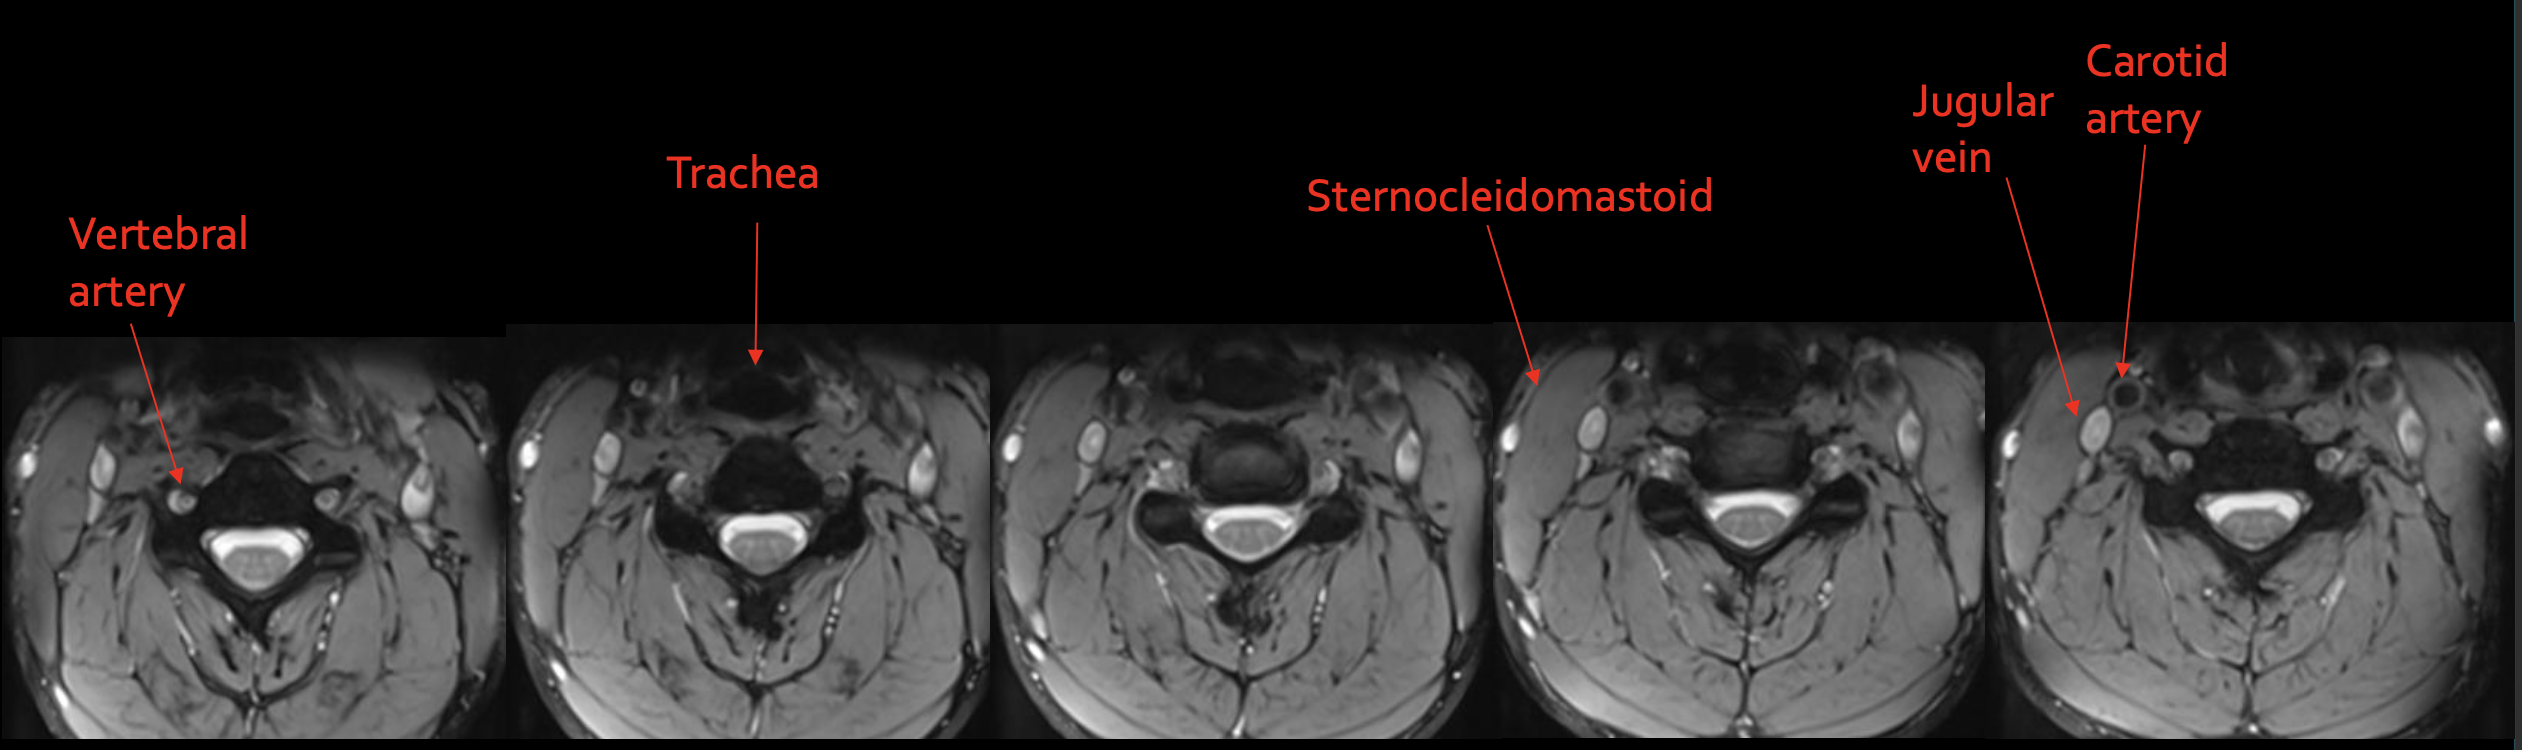

椎动脉

Vertebral artery

气管

Trachea

胸锁乳突肌

Sternocleidomastoid

颈内静脉

Jugular vein

颈动脉

Carotid artery